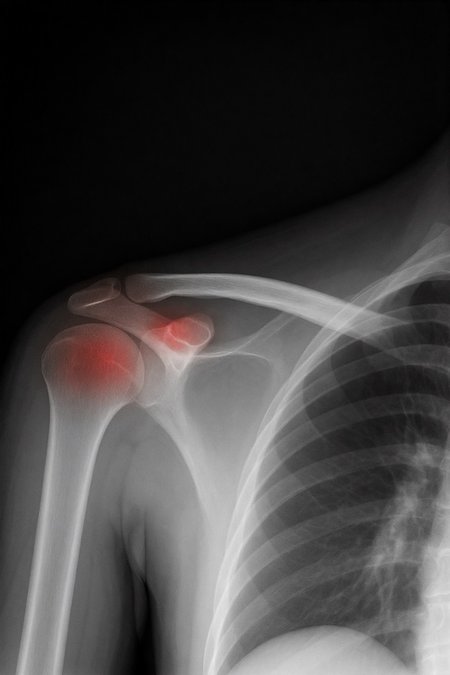

Can a model like Flux Kontext, designed for editing art and photography, be used to work with medical images, for example, with something 'as simple' as red-marking fractures?

The quick answer: it does do something interesting, but it over-scores and is far from reliable as a medical tool. It's a prototype to play with the idea, nothing more.

2. Ask: “Make marks where there is a fracture”.

With a synthetic mini-dataset for Civitai of images made with 100% AI (10 healthy X-rays and 10 fractured):

False positives: 100% in healthy bones.

Fracture detection: ≈ 45%